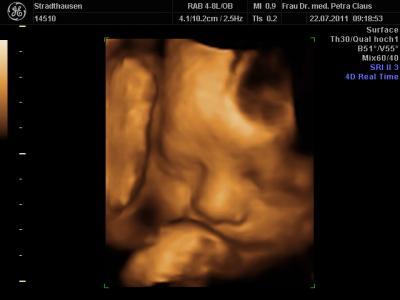

komme grad von der VU und bin ja so ein bisschen megahappy. Endlich hab ich meinen Kleinen wieder im 3D ultralschall gesehen und der war heut vielleicht in Action

...schon beim CTG hat er rumgekaspert, fleißig gegen den Schallkopf getrampelt und sich immer weggedreht, zum Schluss noch nen schönen Schluckauf....voll süß

...alles soweit unauffällig. Dann beim Ultraschall ging es richtig los...Schnute auf, Schnute zu.....wir haben uns köstlich amüsiert. Jedenfalls hat er seinen kleinen Wachstumsrückstand wieder gut aufgeholt, hoffentlich bleibt alles so schön und gesund.

Maße bei 32+4

Gewicht: 2150 gramm

Länge: 42-43 cm....

anbei noch ein paar Bildchen.